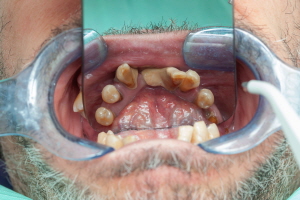

임플란트는 크게 세 가지 구성 요소로 나뉩니다.

- 보철물: 실제 치아 역할을 하는 인공 치아 부분입니다.

- 지대주: 보철물과 픽스쳐를 연결하는 부분으로, 잇몸에 위치하게 됩니다.

- 픽스쳐(고정체): 임플란트의 뿌리 역할을 하며, 잇몸뼈에 고정됩니다.

각 부위에 어떤 재료가 사용되느냐에 따라 가격이 달라집니다. 예를 들어, 보철물은 금속 또는 세라믹으로 만들 수 있고, 픽스쳐는 티타늄 또는 지르코니아 같은 재료를 사용할 수 있습니다.